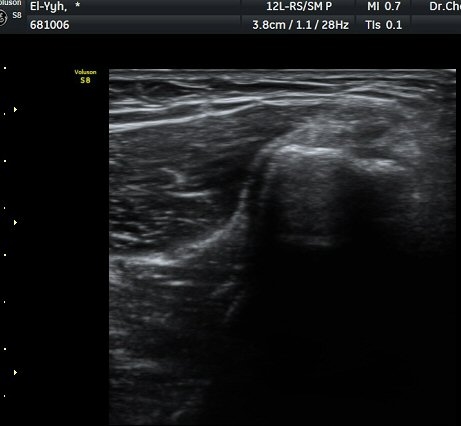

ÃÊÀ½ÆÄ °Ë»ç